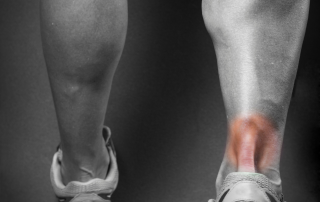

Aşil Tendiniti Nedir? Aşil tendiniti, ayak bileğinin arkasında bulunan ve baldır kaslarınızı topuk kemiğine bağlayan